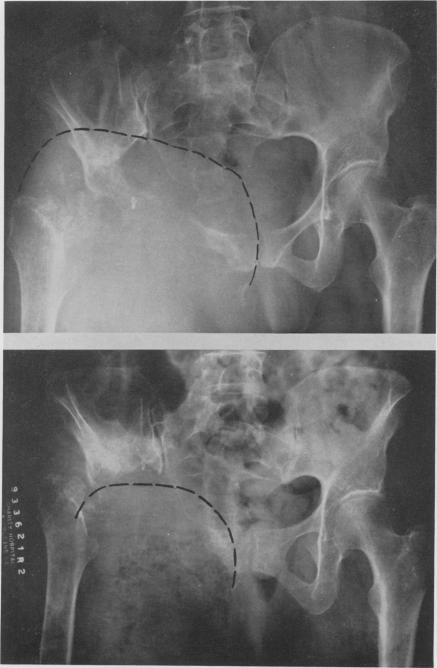

Chemotherapy of cancer: regional perfusion utilizing an extracorporeal circuit.

Ann Surg. 1958 Oct;148(4):616-32. doi: 10.1097/00000658-195810000-00009.